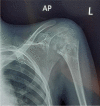

Tuberculosis (TB) remains one of the major public health threats worldwide, despite improved diagnostic and therapeutic methods. Tuberculosis is one of the main causes of infectious disease in the chest and is associated with substantial morbidity and mortality in paediatric populations, particularly in low- and middle-income countries. Due to the difficulty in obtaining microbiological confirmation of pulmonary TB in children, diagnosis often relies on a combination of clinical and radiological findings. The early diagnosis of central nervous system TB is challenging with presumptive diagnosis heavily reliant on imaging. Brain infection can present as a diffuse exudative basal leptomeningitis or as localised disease (tuberculoma, abscess, cerebritis). Spinal TB may present as radiculomyelitis, spinal tuberculoma or abscess or epidural phlegmon. Musculoskeletal manifestation accounts for 10% of extrapulmonary presentations but is easily overlooked with its insidious clinical course and non-specific imaging findings. Common musculoskeletal manifestations of TB include spondylitis, arthritis and osteomyelitis, while tenosynovitis and bursitis are less common. Abdominal TB presents with a triad of pain, fever and weight loss. Abdominal TB may occur in various forms, as tuberculous lymphadenopathy or peritoneal, gastrointestinal or visceral TB. Chest radiographs should be performed, as approximately 15% to 25% of children with abdominal TB have concomitant pulmonary infection. Urogenital TB is rare in children. This article will review the classic radiological findings in childhood TB in each of the major systems in order of clinical prevalence, namely chest, central nervous system, spine, musculoskeletal, abdomen and genitourinary system.